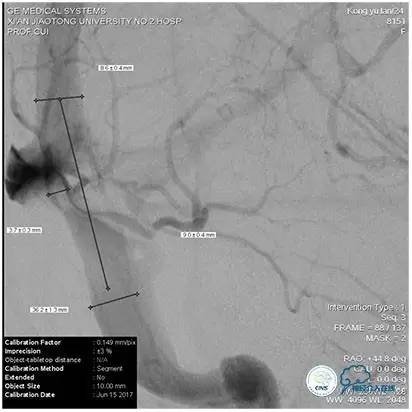

2、术中再次测量血管直径,选择恰当球囊缓慢扩张,避免过度扩张,造成静脉窦与颅骨剥离形成硬膜外血肿;

3、球囊扩张状态下行同侧颈内动脉或椎动脉造影,了解穿支静脉回流状况,如穿支回流缓慢,则选择比静脉窦测量直径小1~2mm的支架;术后发生皮层静脉回流受阻所导致的的梗死、出血风险要小。